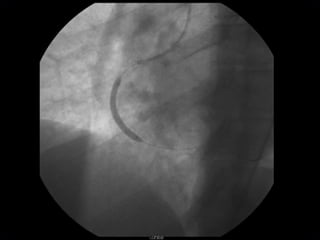

IMPLANTE  STENT